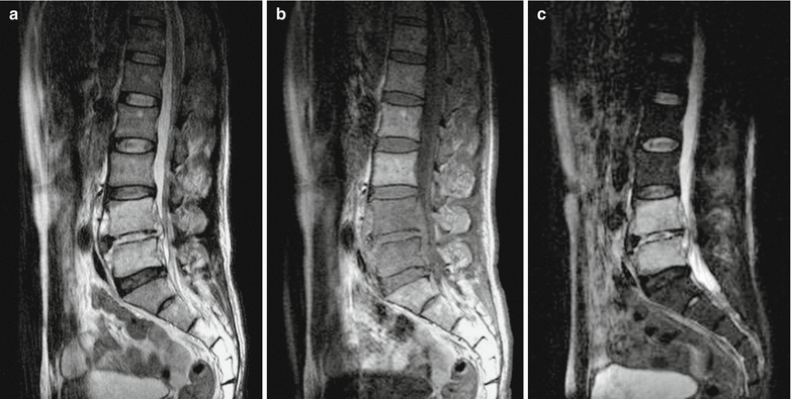

病例四

53岁男性,布鲁氏菌性椎间盘炎。

左图MRI T2矢状位成像,由于L3/L4水平椎间盘和终板受累,呈高强度视野,L4椎体塌陷。中图 MRI T1矢状位呈低信号强度。右图 MRI T矢状位影像增强 显示L3、L4椎体增强,符合椎间盘炎。硬膜外脓肿形成并向L4/L5水平延伸。